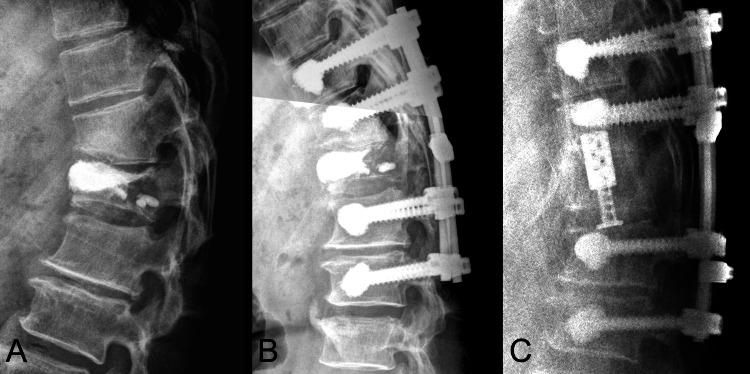

While osteoporosis is the primary cause of vertebral compression fractures (VCFs), it's crucial to promptly recognize pathological fractures through comprehensive diagnostic tests, including vertebral biopsies, to determine the exact etiology. For instance, a 66-year-old male with osteoporosis experienced worsening lower limb weakness and back pain after an initial vertebroplasty for a T12 compression fracture. Subsequent MRI revealed severe circumferential extradural compression at T12, leading to further surgeries that eventually uncovered metastatic adenocarcinoma from a pancreatic tumor. This case highlights the importance of precise diagnosis through vertebral biopsy and the necessity of sufficient ventral decompression or corpectomy, coupled with extensive laminectomy, to address severe neurological impairments like paraplegia. Prompt and accurate interventions can significantly improve patient outcomes and quality of life.

摘要

虽然骨质疏松症是椎体压缩性骨折(VCF)的主要原因,但通过包括椎体活检在内的全面诊断测试及时识别病理性骨折以确定确切病因至关重要。例如,一名患有骨质疏松症的66岁男性在接受T12压缩性骨折的初次椎体成形术后,下肢无力和背痛加重。随后的MRI显示T12水平存在严重的环形硬膜外压迫,导致进一步手术,最终发现是胰腺肿瘤转移所致的腺癌。该病例强调了通过椎体活检进行精确诊断的重要性,以及为解决诸如截瘫等严重神经功能障碍而进行充分的前路减压或椎体切除并结合广泛椎板切除术的必要性。及时准确的干预措施可显著改善患者的预后和生活质量。